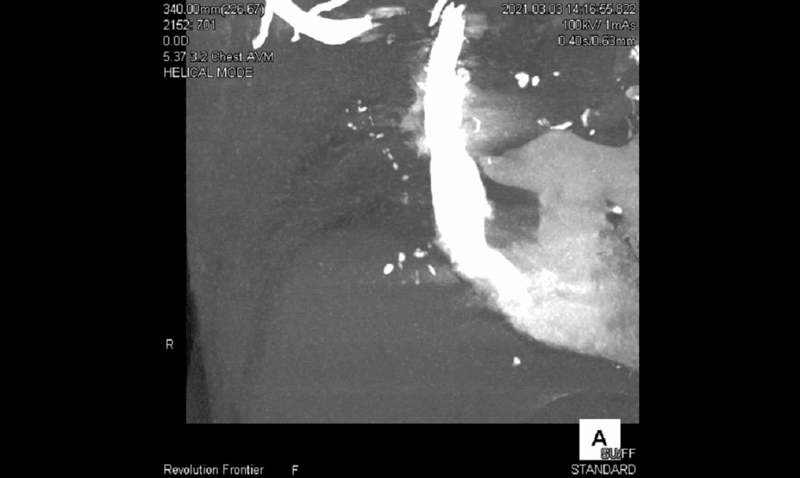

図2に撮影で得られた4D-MIP画像を提示します。肺動脈相で右肺動脈は描出されず、大動脈相で肋間動脈および右下横隔動脈の拡張を認めました。また右肺静脈が描出されるのと同時に、肺動脈の残余が逆行性に造影されたため、右肺動脈の血流途絶のため肋間動脈が代償的に肺を潅流していると考えられます(図2)。

Frontier_Chibadaigaku_01_04.gif

図2 Shuttle画像の4D-MIP

画像作成においては、非造影の時相をマスク画像として、各時相でサブトラクションを用いることにより、肋骨に囲まれた胸壁を走る肋間動脈や内胸動脈などの血管を描出することができます。またマルチフェーズの画像を用いることで、CT値の高いフェーズを選択でき、各血管を末梢まで描出した3D画像を再構成することができ、より質の高い手術支援画像を提供することができます。